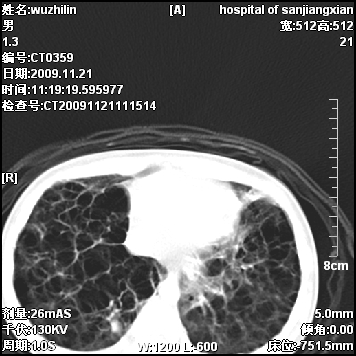

标题: PED3072: 1岁3个月患儿 胸部弥漫性病变 [打印本页]

标题: PED3072: 1岁3个月患儿 胸部弥漫性病变

弥漫性薄壁囊腔,胸膜下及肺底部占优势,双上肺磨玻璃密度影,首先考虑特发性肺间质纤维化,其次囊性肺纤维化,肺淋巴管平滑肌瘤病嗜酸性肉芽肿等;要结合临床综合考虑。

两肺布满多个薄壁含气囊腔,以下肺居多,伴磨玻璃样密度影,左侧气胸。两肺发育不全、两肺多发肺囊肿并感染,其次考虑肺囊腺瘤。